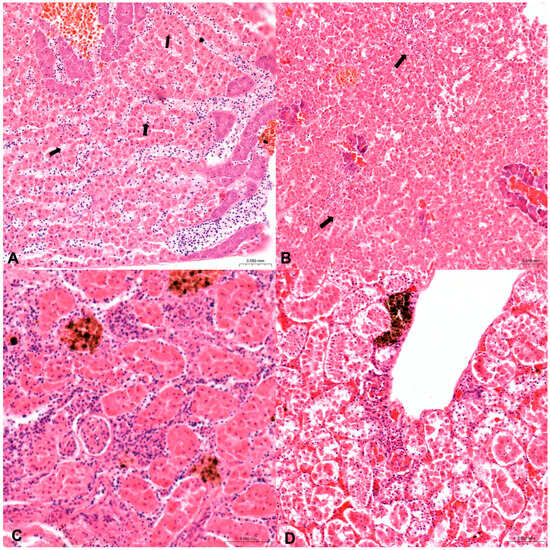

3.2. Histopathological Examination

3.3. Immunohistochemical Examination